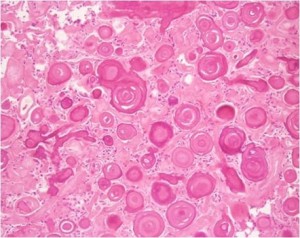

Psammoma body (derived from the Greek word psammosmeaning “sand”) is a round collection of calcium, seen microscopically. They usually have a laminar appearance; are circular, acellular and eosinophilic in histology.

- They are mineralized bodies composed usually of a central capillary surrounded by concentric whorls in various stages of hyaline change and mineralization